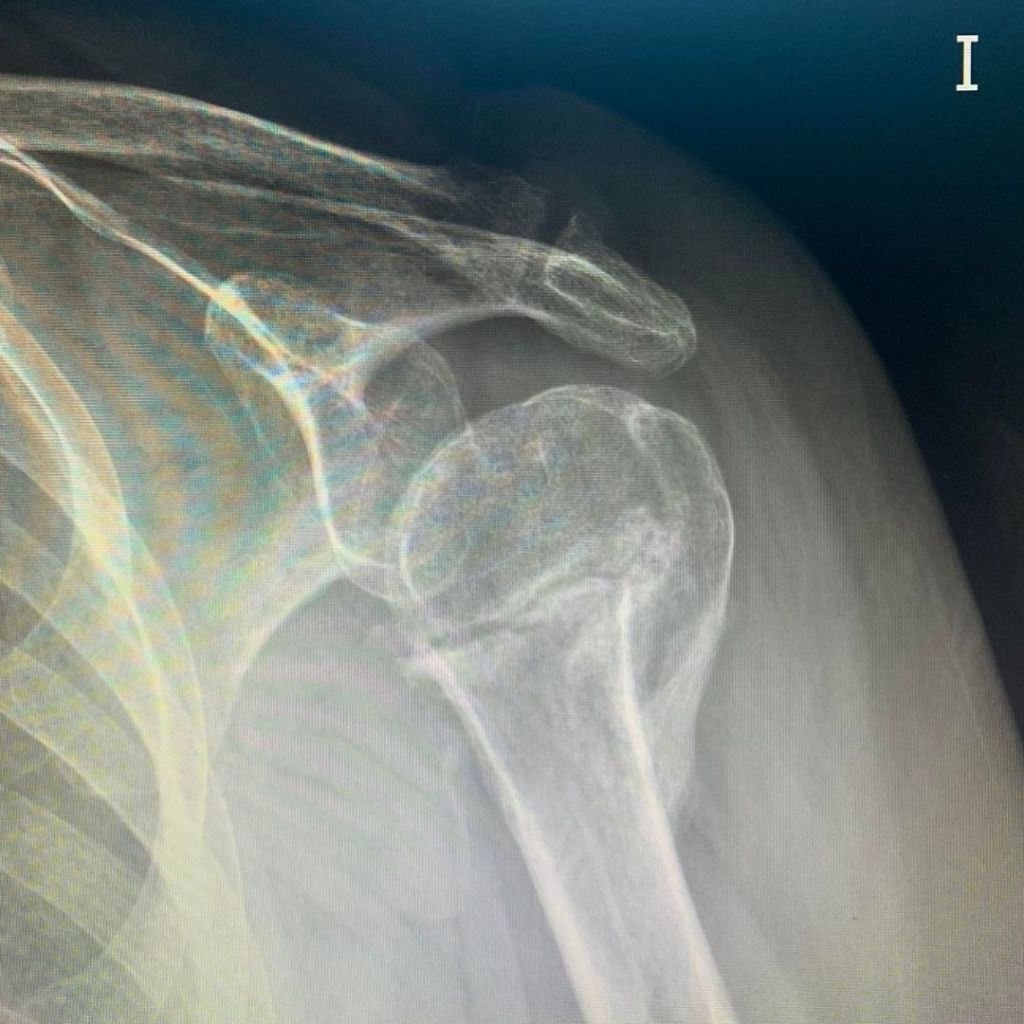

Se comienza con tratamiento de Magnetoterapia durante un mes asociado a terapia manual para el resto de limitaciones en el miembro superior izquierdo que tenía por la inmovilización tan prolongada. Con un mes de tratamiento se realiza un estudio radiológico (Fig. 2) que demuestra que la fractura ha generado un callo, consiguiendo la consolidación suficiente para comenzar a mover su hombro y, sin necesidad de tratamiento con antiinflamatorios, pudo descansar por las nochces sin tener que levantarse por el dolor nocturno. Con todo ello, con la combinación de la Magnetoterapia y la Terapia Manual hemos evitado una cirugía a la paciente.